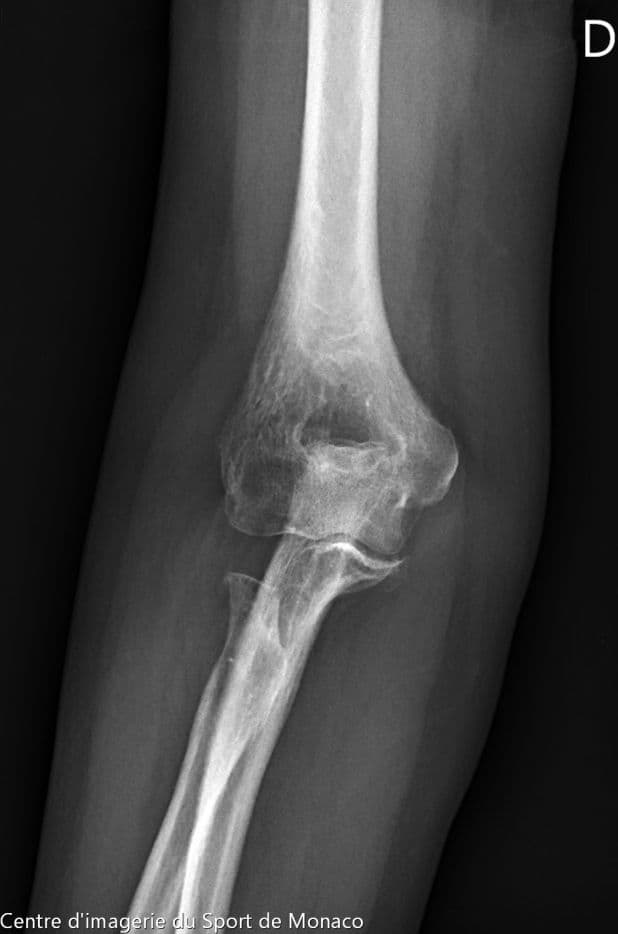

Radiographie

Excroissance osseuse au niveau métaphysoépiphysaire de la tête radiale qui évoque un ostéochondrome à large base d’implantation

Aspect post chirurgical de résection de la tête radiale.